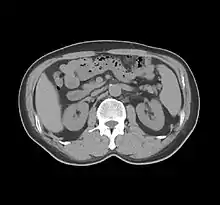

His name is immortalised in the Hounsfield scale, a quantitative measure of radiodensity used in evaluating CT scans. The scale is defined in Hounsfield units (symbol HU), running from air at −1000 HU, through water at 0 HU, and up to dense cortical bone at +1000 HU[12][13] and more.

While on an outing in the country, Hounsfield came up with the idea that one could determine what was inside a box by taking X-ray readings at all angles around the object. He then set to work constructing a computer that could take input from X-rays at various angles to create an image of the object in "slices". Applying this idea to the medical field led him to propose what is now known as computed tomography. At the time, Hounsfield was not aware of the work that Cormack had done on the theoretical mathematics for such a device. Hounsfield built a prototype head scanner and tested it first on a preserved human brain, then on a fresh cow brain from a butcher’s shop, and later on himself. On 1 October 1971, CT scanning was introduced into medical practice with a successful scan on a cerebral cyst patient at Atkinson Morley Hospital in Wimbledon, London, United Kingdom.[16] In 1975, Hounsfield built a whole-body scanner. The principles of computed tomography developed by Hounsfield remain in use today (2022).